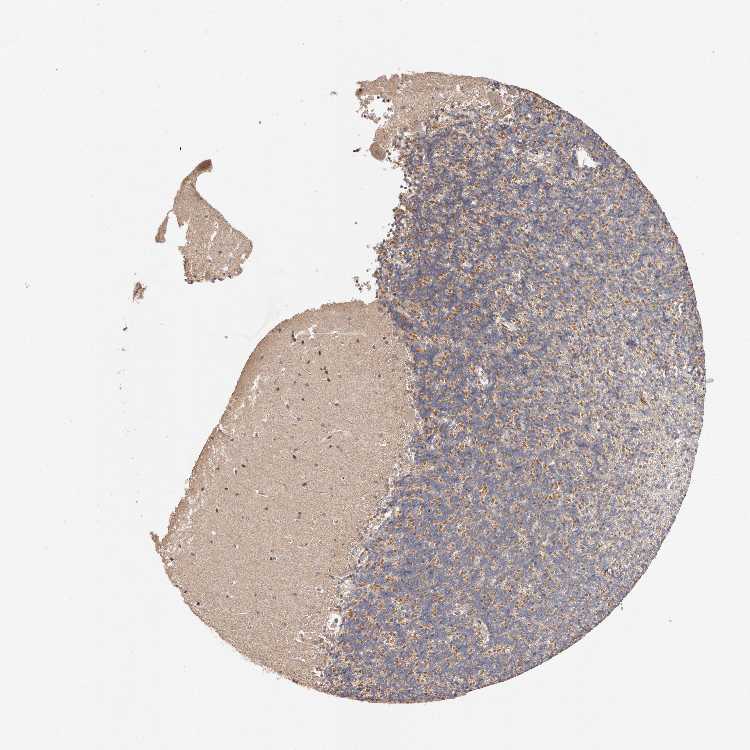

CEREBELLUM - Antibody stainingi

Antibody staining in the annotated cell types in the current human tissue is reported as not detected, low, medium, or high, based on conventional immunohistochemistry profiling in selected tissues. This score is based on the combination of the staining intensity and fraction of stained cells.

Each image is clickable and will lead to virtual microscopy that enables deeper exploration of all samples and also displays staining intensity scores, fraction scores and subcellular localization as well as patient and tissue information for each sample.

Antibody HPA005719

Purkinje cells Medium

Cells in granular layer Medium

Cells in molecular layer Medium